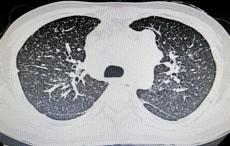

阳光讯(记者 郑亚雷)11月19日是第24个“世界慢阻肺日”,今年的主题是:“呼吸不畅,当心慢阻肺病”。为提高公众对慢阻肺的认知,推动“早预防、早发现、早治疗”理念深入人心,西安市中心医院呼吸与危重症...

阳光讯(记者 郑亚雷 通讯员 蔡豪然)在第24个世界慢阻肺日来临之际,西安市红会医院呼吸内科在南院区门诊大厅举办了主题为“呼吸不畅,当心慢阻肺”的大型义诊活动。本次义诊专家团队由呼吸内科李晓利主任和科...

阳光讯(记者 郑亚雷)11月19日,第24个世界慢阻肺日如期而至,今年主题为“呼吸不顺畅,当心慢阻肺”。当日上午,西安市第九医院门诊大厅人头攒动,呼吸与危重症医学科牵头举办的大型义诊活动温暖启幕,为市...